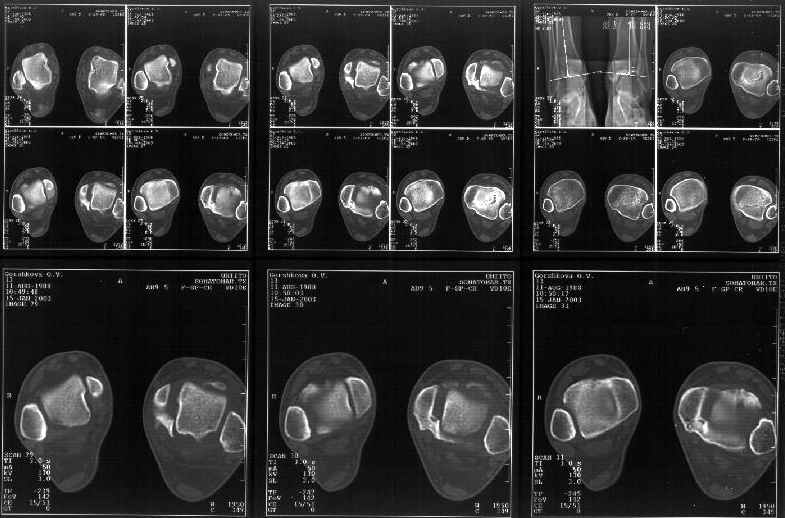

Мне в тоже время совершенно ясно видно по той же КТ, по 4 срезам, расположенным в центре и вверху пленки, что перелома внутренней лодыжки не было, в следующем собщении я приложу увеличенный фрагмент томограммы. А к этому письму прилагаю увеличеный фрагмент послеоперационной рентгенограммы, где выделил отколотый фрагмент

позади внутренней лодыжки. И он, как я вижу, находится между стержнем и тараном. А перелома внутренней лодыжки, и тем более смещения, IMHO

не определяется.

Отправитель: Alexander Chelnokov 12 Январь 2003, 14:55

Здесь 4 среза, начиная от основания лодыжки и проксимальнее. Где, по Вашему мнению, проходит линия перелома, отделяющая переднюю часть внутренней лодыжки от большеберцовой кости? Заранее спасибо.

Сегодня пациентке сделали сравнительную КТ. А ксиальные и Фронтальные срезы приложены. Ваше мнение?

Фронтальные

Аксиальные